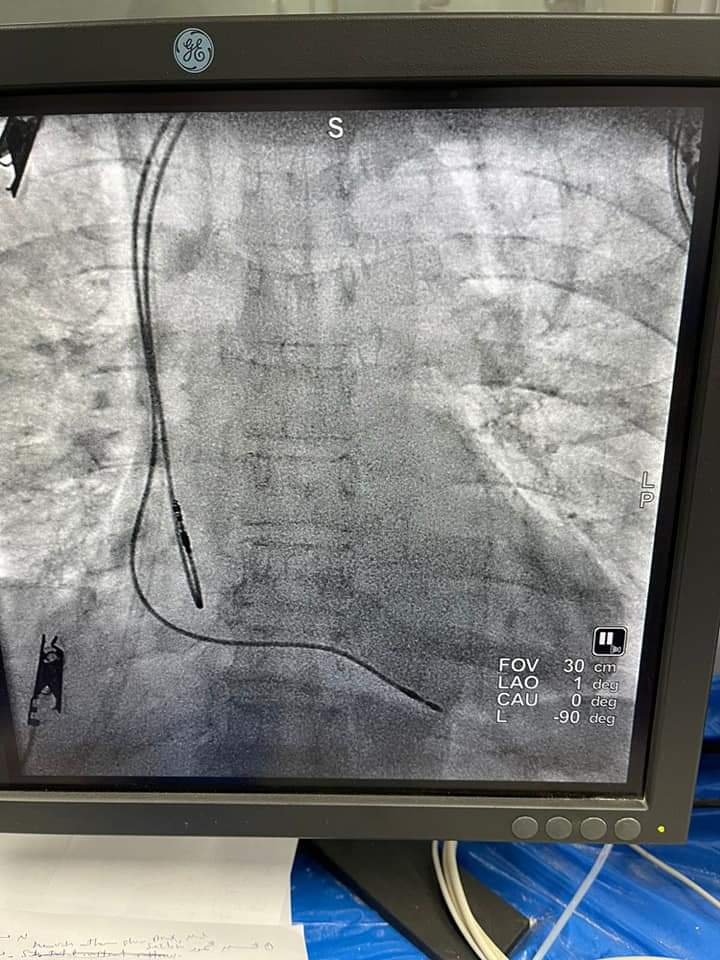

نجح فريق طبى بمستشفى بنها التعليمي بمحافظة القليوبية، بقيادة الدكتور وائل مقلد رئيس قسم القلب بالمستشفى وبمعاونة الدكتورة امل محمود اخصائي كهربية بزرع اول جهاز منظم ضربات قلب ثنائي الحجرات لمريضة تعانى من قطع كامل بالضفيرة الكهربية.

وأشارالدكتور وائل مقلد رئيس قسم القلب بالمستشفى تم حجز المريضة بالمستشفى لمدة عده أيام وعمل الفحوصات الطبية اللازمة للحالة، منوها ان حالة المريضة مستقرة حالياً